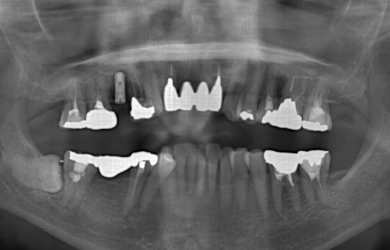

治療方針 ブリッジの支えとなっている歯の寿命を延ばすため、ブリッジの部分を切断し、インプラント治療を施す。

治療内容 インプラント1本、ハイブリッドセラミック1本、ジルコニアオールセラミック8本

治療前

• 治療前